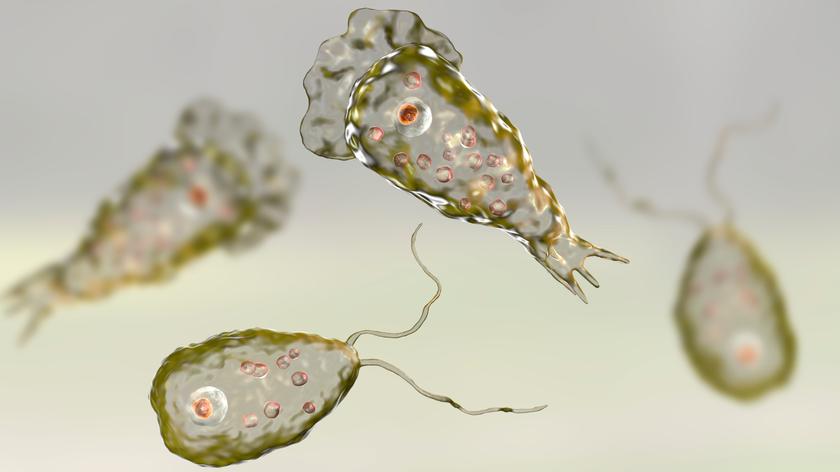

Slzovnička zhubná

Najdesivejšia vec na tomto parazitovi je snáď to, že len veľmi ťažko ju lekári dokážu diagnostikovať a v prípade, že sa im to aj náhodou podarí, liečba nie je k dispozícii – a aby toho nebolo málo, je až 97% pravdepodobnosť, že vás čaká smrť.

Tento parazit sa radí k amébam a nakaziť sa môžete pri plávaní alebo potápaní (v horúcich prameňoch, riekach, jazerách v tropickom prostredí), kedy sa vám do nosa dostane voda spolu s touto amébou – tá následne cez nervy prechádza až do mozgu – kde rozkladá mozgové tkanivo, takže o niekoľko dní budete mŕtvy.